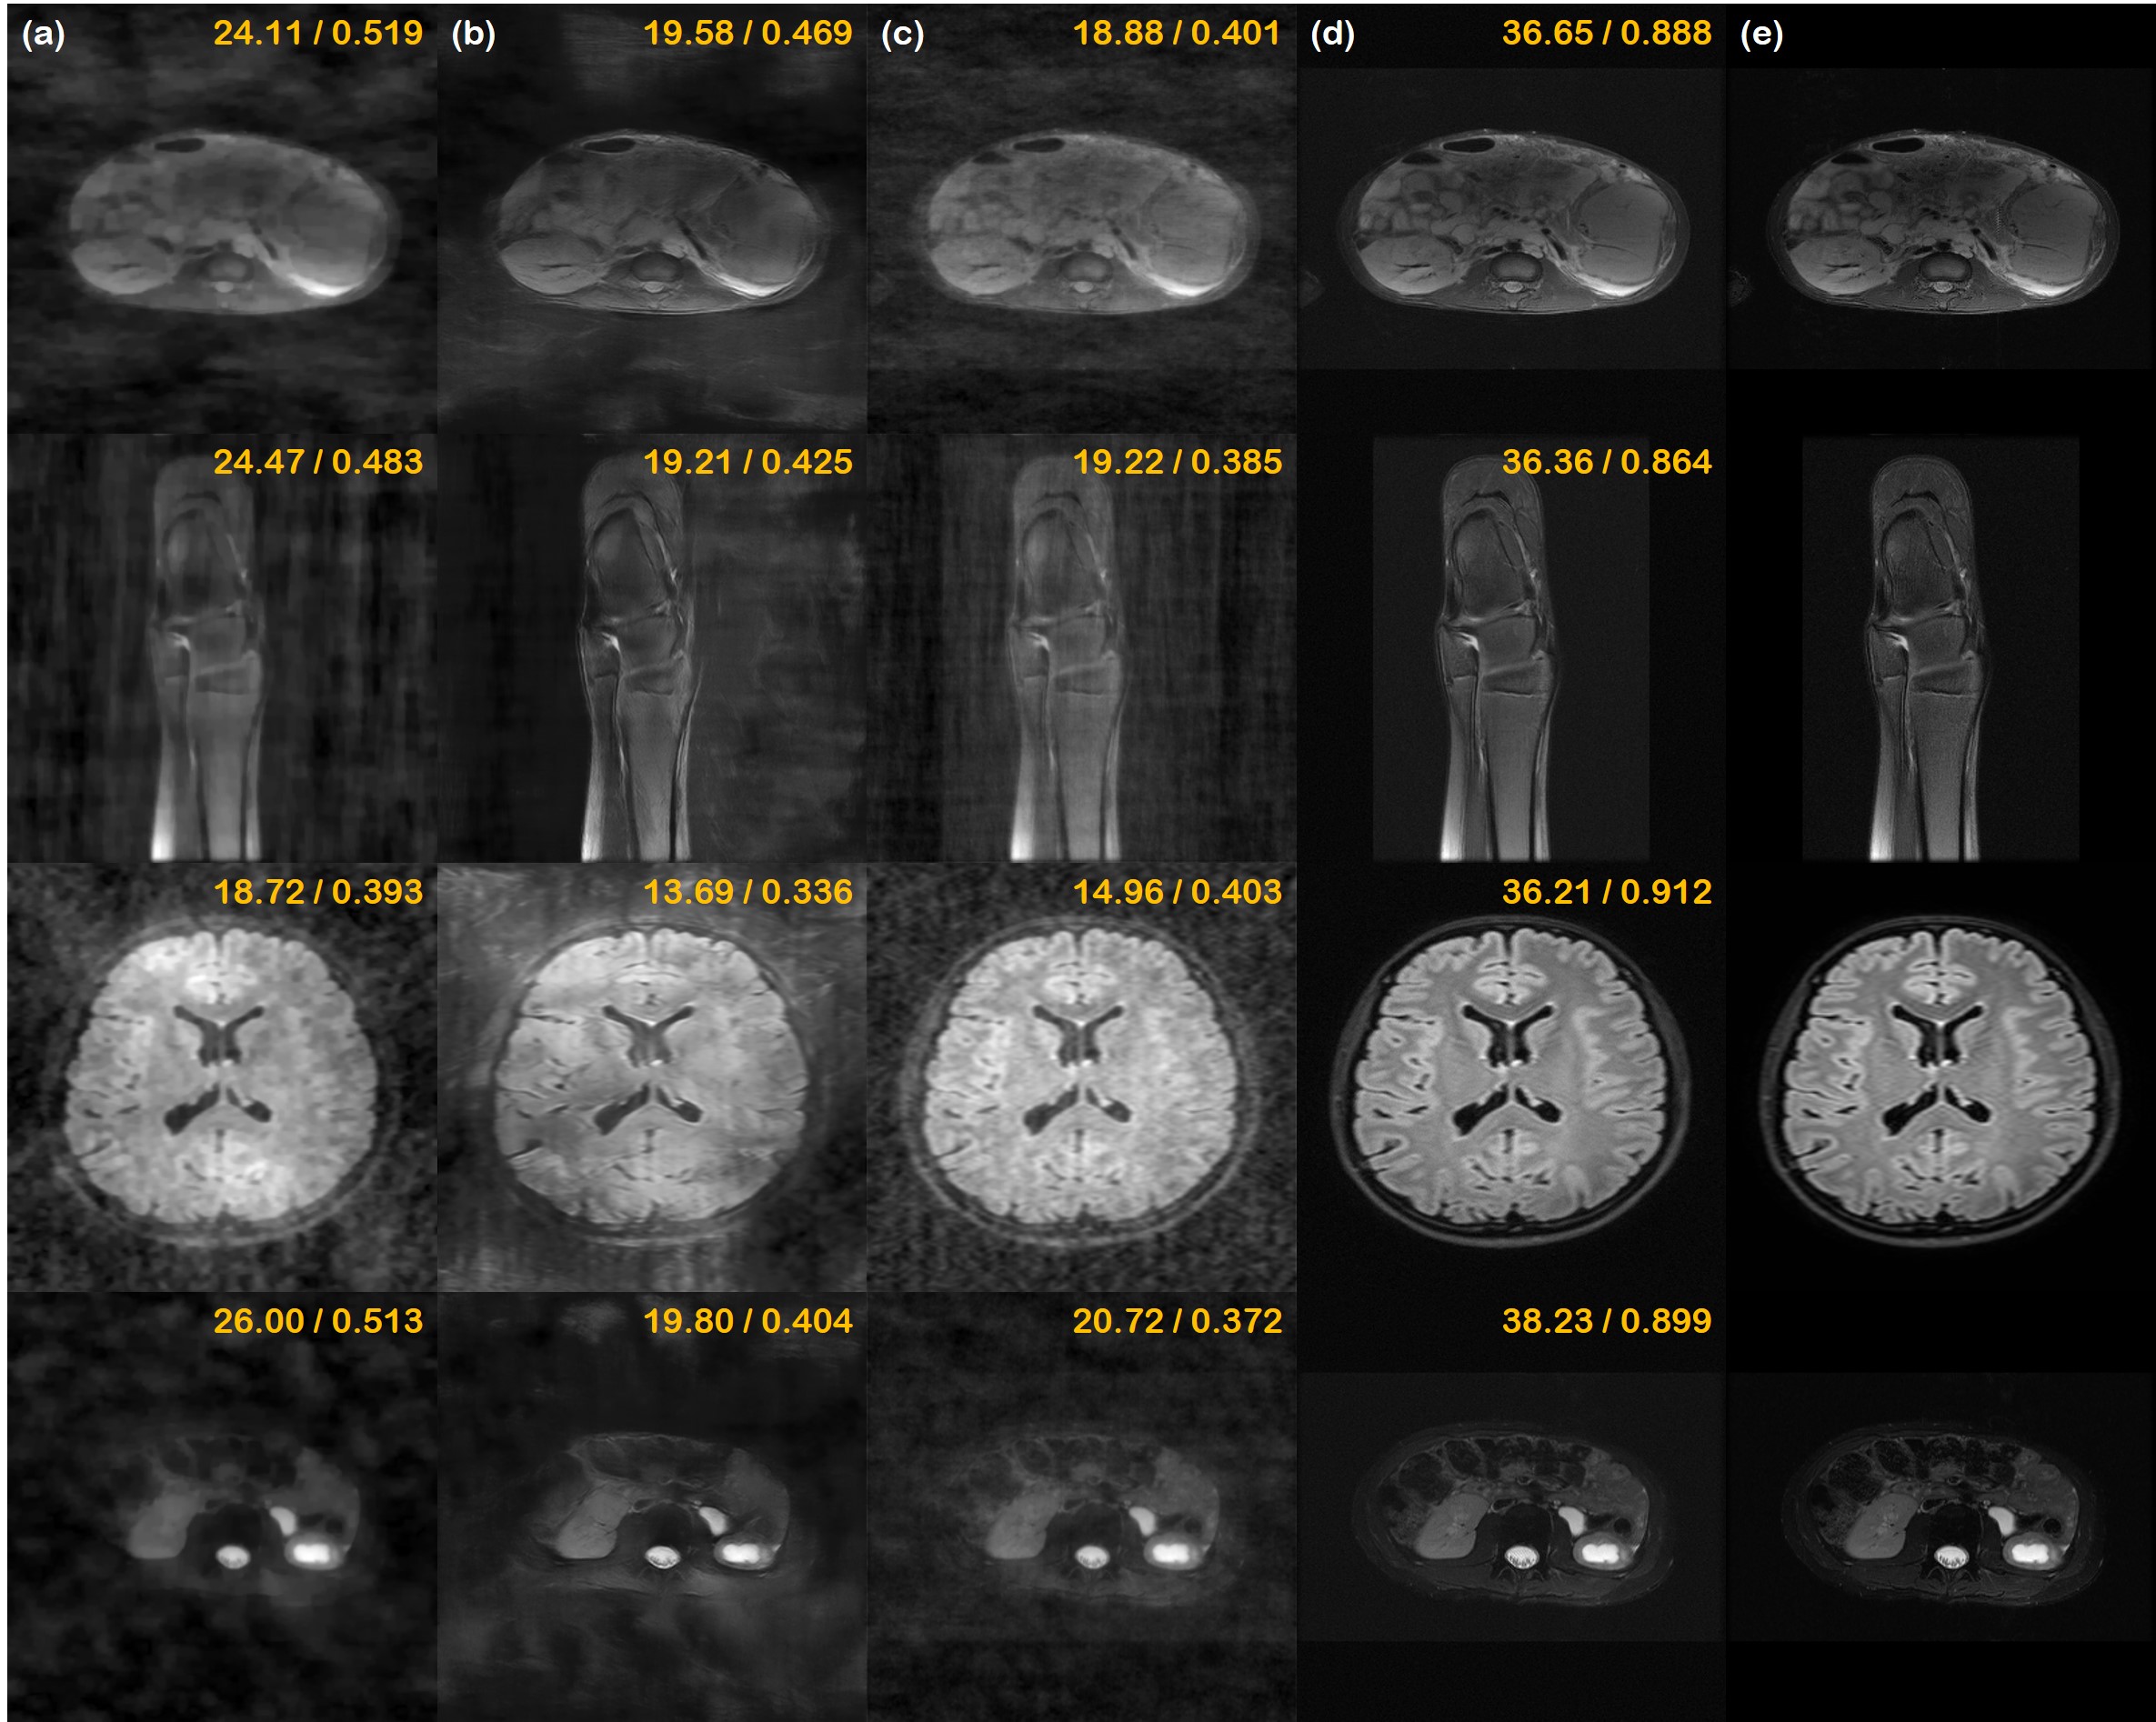

Refer to caption

Fig. 3: Reconstructions of the real-valued simulation study. (a) Sub-sampling mask used to generate under-sampled image, (b) TV, (c) supervised learning (U-Net) (d) DuDoRNet [68], (e) proposed method, and (f) ground truth. 1stst{}^{\text{st}} row: 2D ×8absent8\times 8 Gaussian random sampling, 2ndnd{}^{\text{nd}} row: 1D ×4absent4\times 4 uniform random sampling, 3rdrd{}^{\text{rd}} row: 1D ×8absent8\times 8 Gaussian random sampling, 4thth{}^{\text{th}} row: ×15absent15\times 15 variable density poisson disk sampling. Green box: Zoom in version of the indicated yellow box, Blue box: Difference magnitude of the inset (in Viridis colormap). Yellow numbers in the upper right corner indicate PSNR [db], and SSIM, respectively.

5.1 Real-valued Simulation study

First, we show the results of the simulation study using retrospectively under-sampled fastMRI real-valued data of size 320×\times320 in Fig. 3. In the first row, we see reconstructions from 2D ×8absent8\times 8 Gaussian random sampling, which is the sub-sampling pattern that induces the least aliasing artifact. Here, we see that the proposed performs nearly perfect reconstruction, where we see virtually no structural difference even in the zoomed-in image. Reconstruction through total variation (TV) induces cartoon-like artifacts, and cannot remove the overall foggy artifacts across the whole image. U-Net and DuDoRNet produce blurry reconstructions that are suboptimal, which indicates that they cannot adapt to different sampling patterns that were not seen from the training process.

In the second row, we compare the reconstructions from acceleration using ×4absent4\times 4 uniform random sampling with 4% of the phase encoding lines kept as the autocalibrating signal (ACS) region, producing moderate aliasing artifacts. Even at this level, our method is able to provide accurate reconstruction, capturing most of the high-frequency details of the ground truth. In this acceleration factor, TV is not able to completely remove the aliasing artifacts. The averaging effect of supervised reconstruction now becomes more clear, often omitting the important details of the scan. Reconstruction with DuDoRNet also suffers from leftover aliasing artifacts in this regime, even though this is just a slight difference in the sampling pattern.

The third row shows ×8absent8\times 8 Gaussian random sampling (4% ACS region). TV only partially removes the artifacts, while introducing quite an amount of cartoon-like artifacts. Supervised U-Net and DuDoRNet smooths away a lot of details, producing unrealistic texture. Surprisingly, even at this level of acceleration factor, our method provides a fairly accurate reconstruction, matching most of the details from the ground truth.

In the last row, we see the most aggressive under-sampling factor - ×15absent15\times 15 variable density poisson disk under-sampling. Thanks to the evenly spread out k𝑘k-space samples, this sampling scheme is considered one of the state-of-the-art amongst the various sampling patterns, which produce the least artifacts given the same budjet [14]. Here, similar to what was seen with 2D Gaussian sampling, only the proposed method is able to produce high-fidelity image reconstruction. Other methods still suffer from severe artifacts, with blurred-out details.

We provide a thorough comparison of quantitative metrics on the test set in Table 1. On all the different sampling patterns, our method significantly outperforms the comparison methods and is on par with the state-of-the-art DuDoRNet [68] in Gaussian 1D sampling pattern. Results of RM-ANOVA also indicates that the superiority of the proposed method is statistically significant against all other methods in most cases.